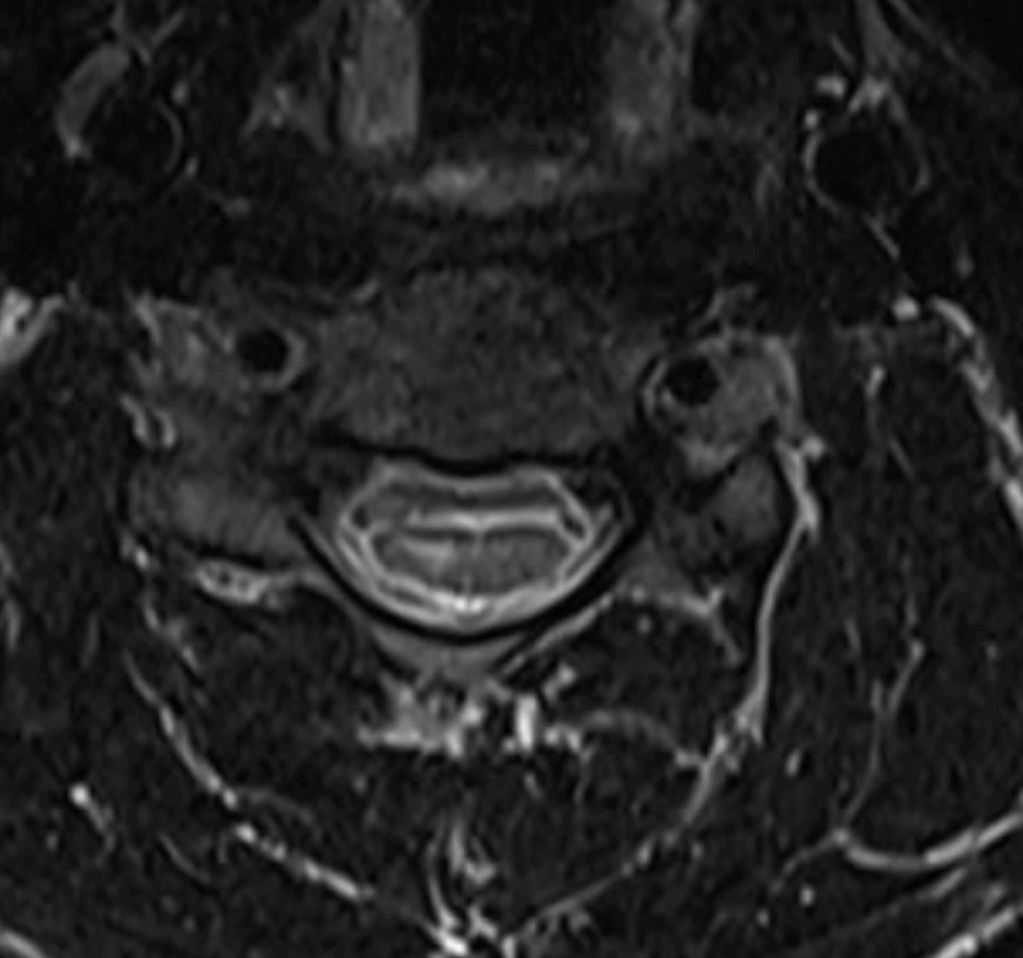

Neutral position: Axial T2 MRI of cervical spine showing right hemicord signal changes